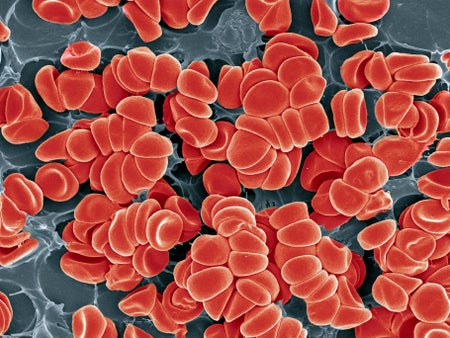

Solving Inflammatory Bowel Disease’s Mysteries May Lead to New Therapies

Understanding genetics, immunology and the microbiomes of people with inflammatory bowel disease could aid in finding the right treatments for the condition

Cells Organize Themselves into ‘Neighborhoods’ That Could Shape Treatment

“Cell atlases” offer an unprecedented look at how kidney cells become diseased and how fetal cells invade and remodel the placenta’s blood vessels